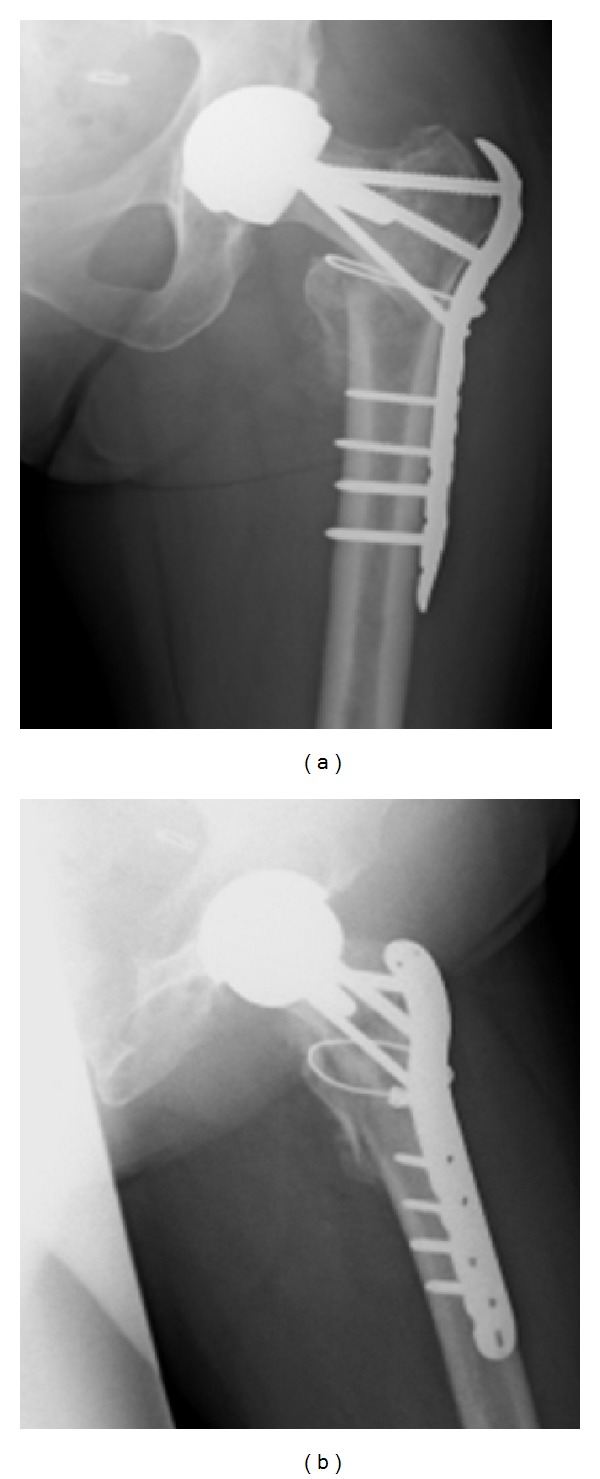

At 12 weeks post-operatively, it was noted that there was good callus formation at the fracture site and that the fracture appeared to have stabilised, with no evidence of metalwork failure (see Figure 6). Mrs X was advised to wean herself off crutches and was referred for physiotherapy.

Figure 6.

(a)-(b) Radiographs from 12 weeks after operation.